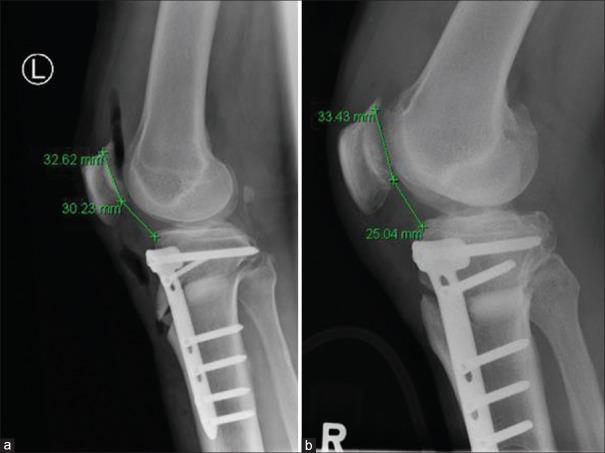

We conducted a retrospective study in patients who underwent HTO in our center between September 2009 and February 2017. Preoperative and 6-week postoperative long-leg weight bearing films and lateral knee radiographs were assessed. Pre- and postoperative radiological measurements include the Caton-Deschamps Index (CDI), the mechanical axis deviation (MAD), and the posterior TS. Independant -test and Pearson correlation test were performed.

A total of 106 knees were recruited. The mean age was 48.8 ± 10.8 years. 66 (62.3%) and 40 (37.7%) knees were from males and females, respectively. The mean pre- and postoperative measurements was (-9.70° ± 3.67° to 0.08° ± 2.80°) (-varus; +valgus) for the MAD, (7.14° ± 1.78° to 8.72° ± 3.11°) for posterior TS, and (0.93° ± 0.084° to 0.82° ± 0.13°) for CDI ( ≤ 0.001 for all). The association between patella height change and the level of osteotomy (supra-tubercle vs. infra-tubercle) was statistically significant ( < 0.001). A supra-tubercle osteotomy cut significantly lowering patella height ( = 0.011). There was otherwise no statistically significant correlations between patella height changes and the correction angle ( = 0.187) or posterior TS change ( = 0.744).

A medial opening wedge HTO above the tibial tubercle was significantly associated with lowering patella height or reducing CDI postoperatively. Based on our results, we would recommend the use of an infra-tubercle osteotomy during the corrective surgery to prevent the complication of patella baja.

我们对2009年9月至2017年2月在本中心接受HTO手术的患者进行了一项回顾性研究。评估术前和术后6周的长腿负重片及膝关节侧位X线片。术前和术后的影像学测量包括卡顿 - 德尚指数(CDI)、机械轴偏移(MAD)和胫骨后倾。进行独立样本t检验和Pearson相关检验。

共纳入106个膝关节。平均年龄为48.8±10.8岁。男性膝关节66个(62.3%),女性膝关节40个(37.7%)。MAD术前和术后的平均测量值为(-9.70°±3.67°至0.08°±2.80°)(内翻;外翻),胫骨后倾术前和术后为(7.14°±1.78°至8.72°±3.11°),CDI术前和术后为(0.93°±0.084°至0.82°±0.13°)(所有P≤0.001)。髌骨高度变化与截骨水平(结节上与结节下)之间的关联具有统计学意义(P<0.001)。结节上截骨显著降低髌骨高度(P = 0.011)。此外,髌骨高度变化与矫正角度(P = 0.187)或胫骨后倾变化(P = 0.744)之间无统计学意义的相关性。

胫骨结节上方的内侧开口楔形HTO与术后髌骨高度降低或CDI降低显著相关。基于我们的结果,我们建议在矫正手术中采用结节下截骨以预防髌骨低位并发症。